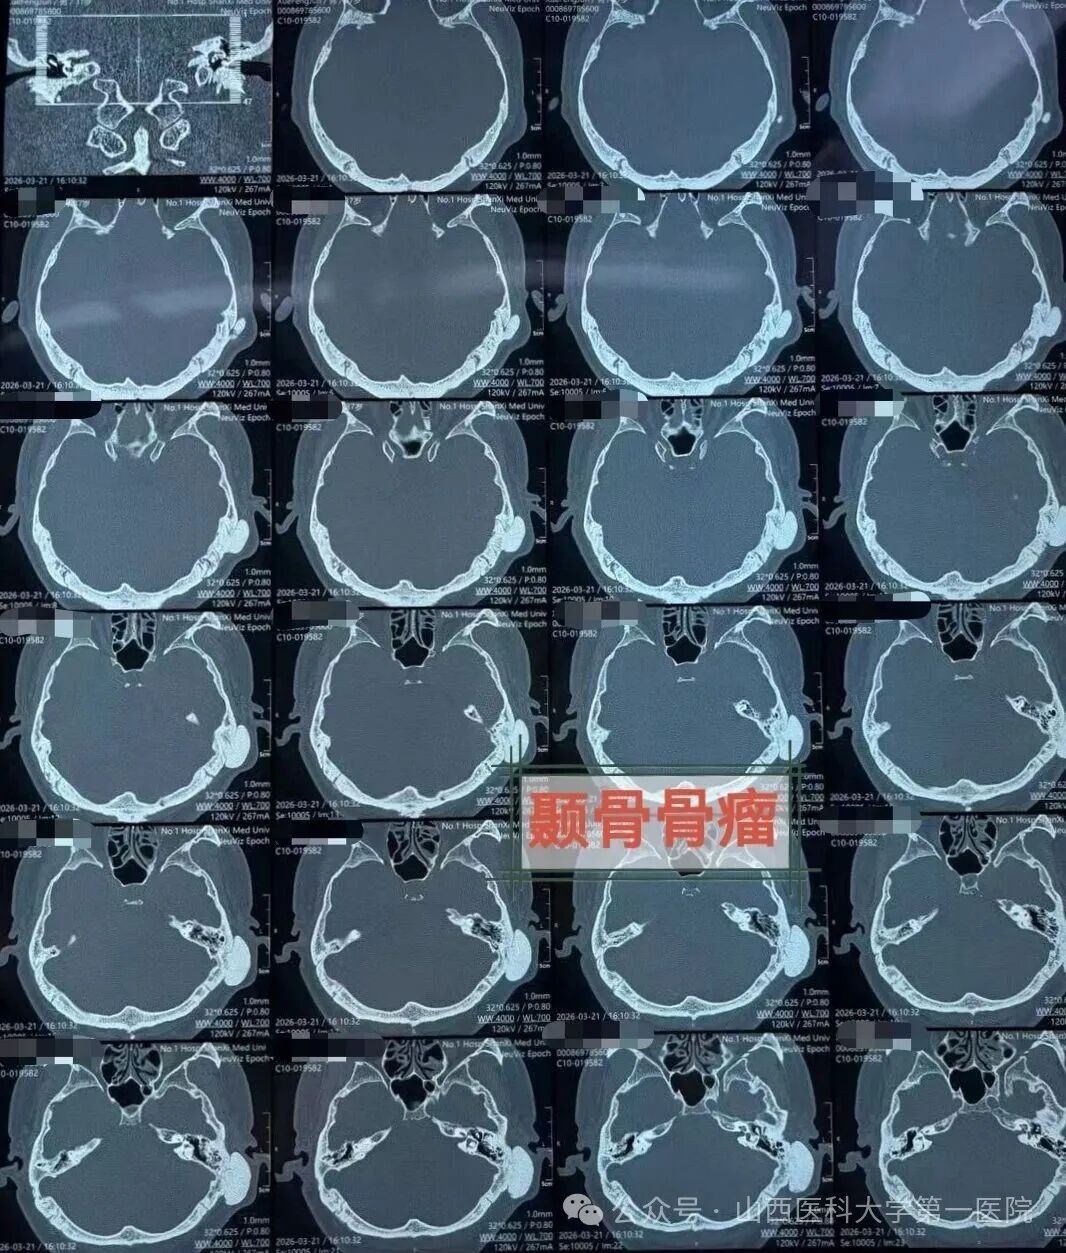

耳鼻咽喉-头颈外科成功施行颞骨骨瘤切除手术

近日,耳鼻咽喉-头颈外科张海利主任医师团队与麻醉科专家紧密协作,成功为一名37岁患颞骨鳞部肿瘤的男性施行了外科切除手术。

患者来自山西晋北,长期受间断性一侧偏头痛及头闷困扰,辗转求医无果,最终来到山医大一院耳鼻咽喉-头颈外科,经颞骨CT及头颅MRI检查,发现左侧颞骨鳞部有一约3.2cm×3.5cm×1.6cm的骨性肿瘤。肿瘤侵犯并破坏了颞骨鳞部、鼓部及乳突,波及颅中窝底,但未突入颅内,与静脉窦等重要神经血管关系密切。

经多学科会诊(MDT)讨论,决定采用经耳后鳞部-乳突进路手术。麻醉科医生实施插管全麻并全程监护,手术室护士密切配合,张海利主任医师与郁文捷副主任医师在显微镜下精准切除乳突及鳞部肿瘤,完好保护了重要血管及神经结构,彻底切除病变。